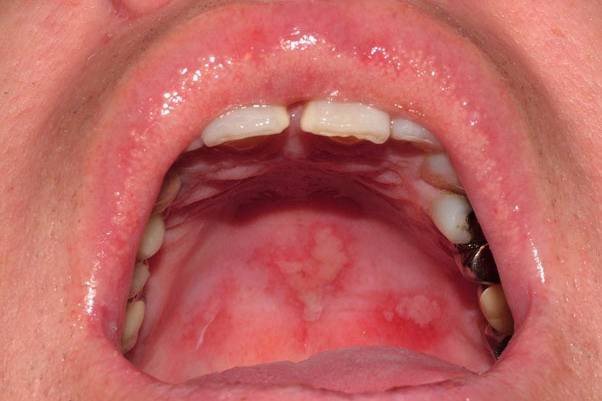

FDEs usually appear as solitary, erythematous, bright red or dusky red macules that may evolve into an edematous plaque; bullous-type lesions may be present. FDEs are most commonly found on the genitalia and in the perianal area, although they can occur anywhere on the skin surface . Some patients may complain of burning or stinging, and others may have fever,

malaise, and abdominal symptoms. FDE can develop from 30 minutes to 8 to 16 hours after ingestion of the medication. After the initial acute phase lasting days to weeks, residual grayish or slate-colored hyperpigmentation develops. On rechallenge, not only do the lesions recur in the same location, but also new lesions often appear.